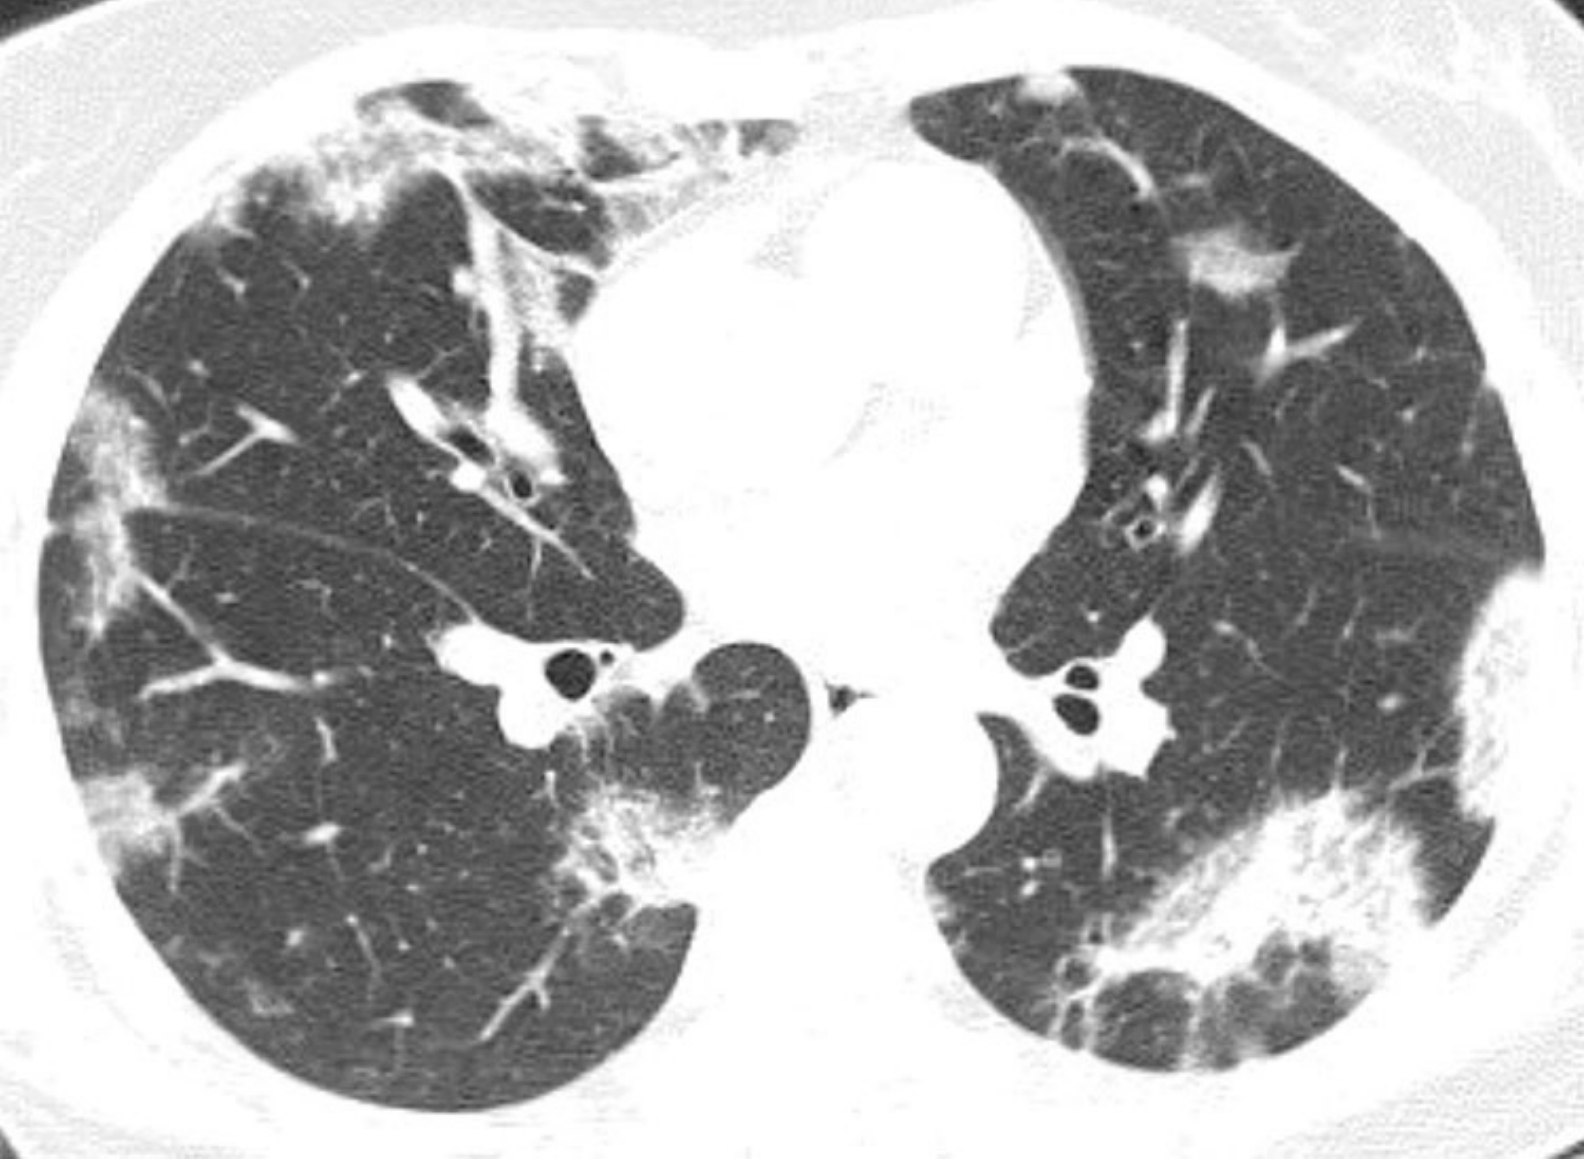

HRCT上异常病变的分布特点有助于区分不同类型的间质性肺炎及鉴别间质性肺炎与其他弥漫性肺部疾病。普通型间质性肺炎、非特异性间质性肺炎及脱屑性间质性肺炎主要表现为肺外周分布为主的异常,累及肺底和肋隔角其余类型的间质性肺炎典型表现为同等累及肺外周部与中央部。其他病因导致的弥漫性肺部疾病(如过敏性肺炎或结节病)通常呈弥漫或中心轴分布,下肋膈角不受累。

d9aa28845b7cba2a1759d5760b020659.png

异常病变的HRCT分布特征在诊断中的价值。

A.纤维型非特异性间质性肺炎相关的硬皮病患者,HRCT显示以肺外周及胸膜下区分布为主的异常表现;

B.结节病患者,HRCT异常表现主要分布在肺门区及支气管周围,而相对未累及胸膜下区。对于慢性症状的病例,胸膜下及肺基底部分布为主的病变提示普通型间质性肺炎、非特异性间质性肺炎或脱屑性间质性肺炎。弥漫性或者中心轴分布是间质性肺炎的不典型分布,提示其他疾病,如过敏性肺炎或结节病。